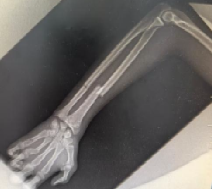

影像科的世界,是我从未接触过的领域。在这里,黑白胶片是“无声的病历”,每一张CT、MRI影像背后,都藏着病灶的密码。带教齐老师教我从影像的灰度、形态中识别病变,从正常组织与异常病灶的对比中寻找线索。老师指着某个细节说“看这里,这是关键”,我才恍然大悟,这段时间的学习,让我对疾病有了更深的印象。